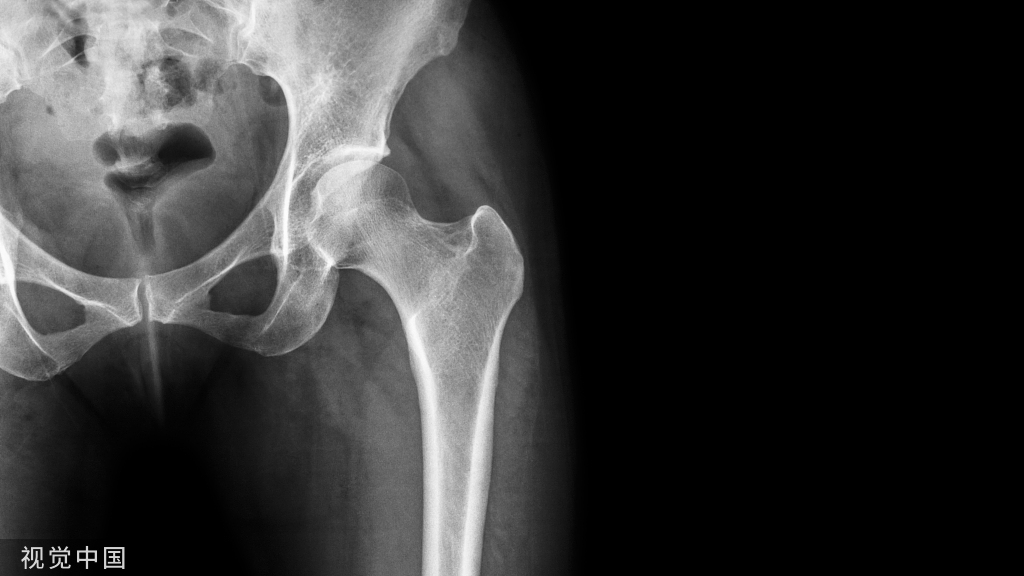

去髓术及根管治疗后牙根折裂,临床表现有多种形式,如牙根横折、根尖裂或根尖纵折等。根折时间长且断裂片移位,在X线片上容易发现;单纯的根裂在X线片上有时较难发现,有的仅见根尖至牙槽嵴顶垂直吸收的稀疏影。有的根折可能术前就已存在,但因未摄X线片而未能发现;有的虽已摄片,但因投照角度失误或阅片经验不足而漏诊。